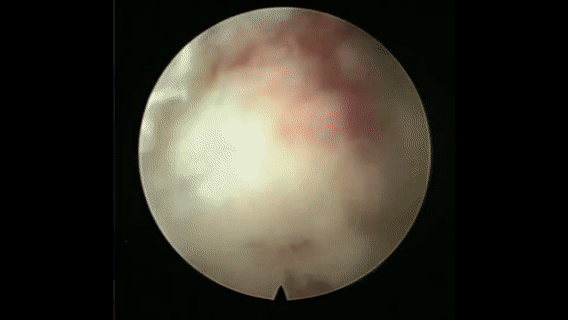

内镜下病灶清除

该手术创伤小、出血少、恢复快,既能彻底清除结核病灶,又能精准稳定脊柱,最大限度保护正常组织,显著降低手术风险,为体质较差患者提供安全有效的解决方案。